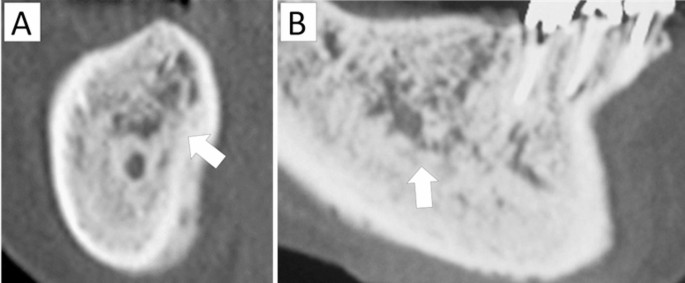

Defined as multiple distinct hypodense areas within dense sclerotic bone:

(−): No mixed-type osteosclerosis.

(+): Mixed-type osteosclerosis observed.

Characterized by an expansile lytic lesion containing a dense central sequestrum, resembling a “bone-within-bone” pattern:

(−): No bone-within-bone appearance.

(+): Bone-within-bone appearance observed.